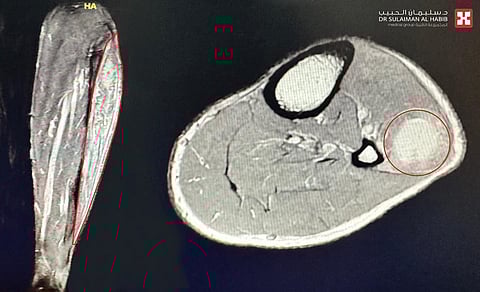

وأوضح أن كامل نتائج الفحوصات أكدت وجود فجوة واضحة في العضلة الشظوية الطويلة للساق، وصعوبة تحريك قدمه اليسرى إلى الأعلى، بالإضافة إلى الكشف عن تجمع دموي موضعي تَسبب في حدوث ضغط شديد على العصب الشظوي؛ مما أدى إلى "سقوط القدم"، هذا بالإضافة إلى وجود قطع طولي كبير في العضلة الشظوية الطويلة.

وأفاد البروفيسور "الجاسر" بأن الفريق الطبي عقب انتهائه من دراسة كامل الفحوصات، قرر التدخل الجراحي.. وبعد اتخاذ كل التدابير الطبية اللازمة لسلامة المريض، أجريت له العملية مستغرقةً 4 ساعات متواصلة، وتم فيها إزالة التجمع الدموي المسبب للضغط على العصب الشظوي، وتحريره، مع التأكد من عمله أثناء الجراحة باستخدام أدوات خاصة لتحفيز تلك الأعصاب، تَبِعَ ذلك إصلاح القطع في العضلة الشظوية الطويلة، نُقِلَ بعدها المريض إلى جناح التنويم.